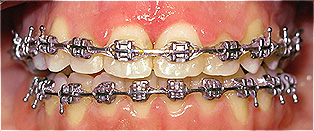

Apinhamento dentário com os dentes caninos em desoclusão (classe II, divisão 2).

![]() |

Após dois anos de tratamento ortodôntico.